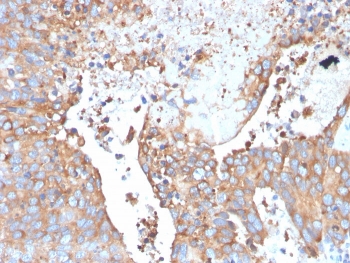

Uroplakin 1B Antibody. Immunohistochemistry analysis of Uroplakin 1B / UPK1B antibody in human urothelial carcinoma tissue using clone UPK1B/3273. FFPE sections show strong HRP-DAB brown membranous staining in tumor epithelial cells with accentuation along the luminal border, consistent with apical surface localization in urothelial cells. This Urothelial Apical Surface Protein Antibody highlights the polarized distribution of UPK1B at the apical membrane of urothelial tumor cells. HIER: boil tissue sections in pH 9 10mM Tris with 1mM EDTA for 20 minutes followed by cooling prior to staining.